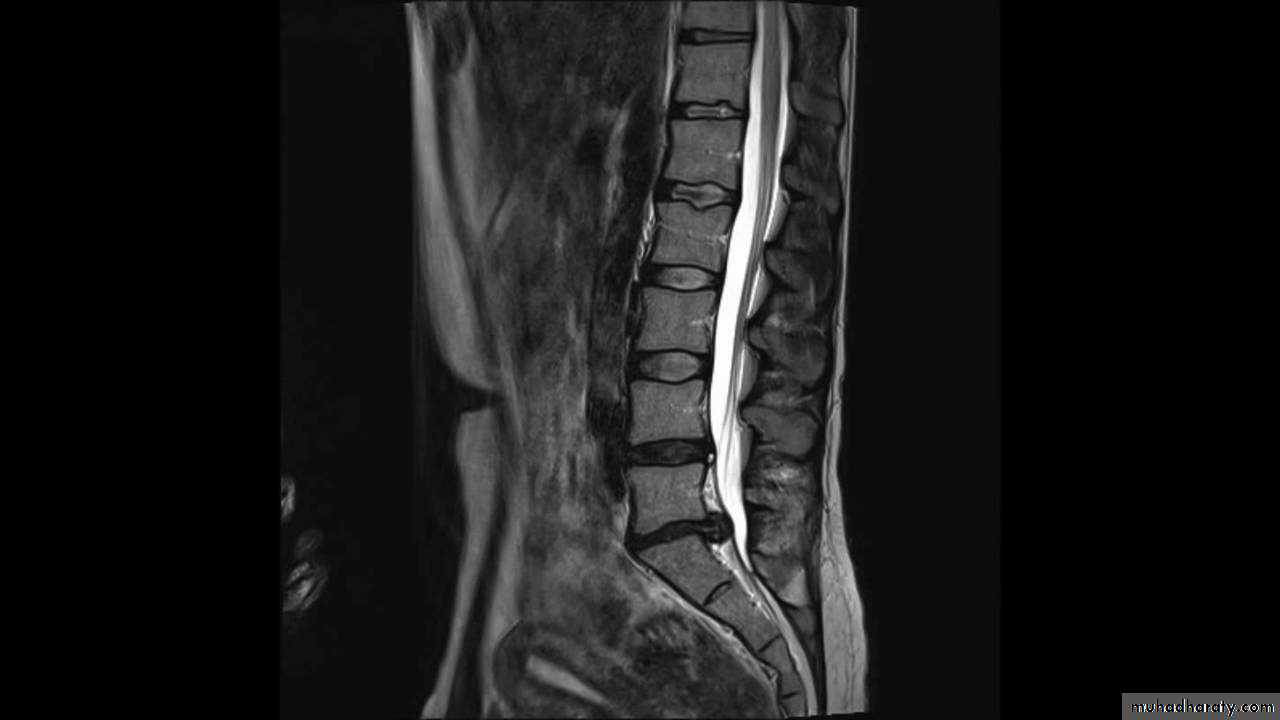

CHRONIC INTERVERTEBRAL DISC DEGENERATIONMRI:

Bulging of the annulus fibrosus in both sagittal and axial projections and diminished thickness and reduced signal intensity (dehydration) of the degenerating disc.

Two measurements are used: the mid-sagittal (anteroposterior) diameter and the inter-pedicular (transverse) diameter of the spinal canal. Normally, the diameters are 15 mm for the anteroposterior and 20 mm for the transverse. Anything less than 11 mm for the anteroposterior diameter and 16 mm for the transverse diameter is considered abnormal.

Imaging:X-rays will show features of disc degeneration or spondylolisthesis. Measurement of the spinal canal can be carried out on CT and MRI.